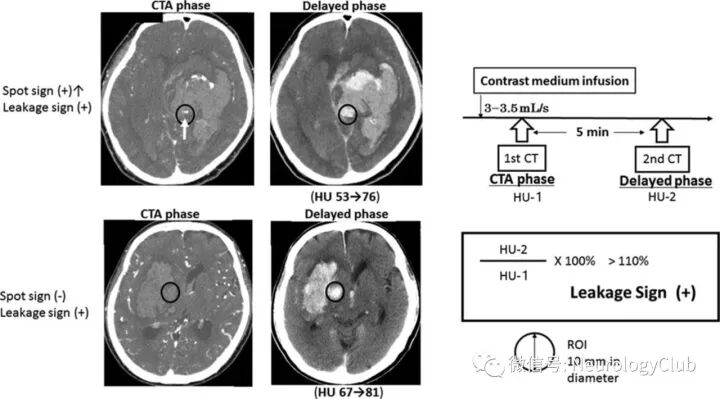

渗漏征

由Orito等于2016年提出,旨在探索比点征更细微的对比剂外渗现象。临床发现其不仅可有效预测血肿扩大,且与预后不良显著相关。每例ICH患者均完成2次CTA扫描,分别为CTA期和延迟期(CTA期后5min),设定直径为10mm的感兴趣区(region of interest,ROI),并计算其CT值,延迟期ROI内CT值较CTA期增加>10%的现象定义为渗漏征。该研究发现渗漏征对预测血肿扩大的敏感性及特异性分别为93.3%及88.9%,均高于点征。

(图2:渗漏征的诊断标准)